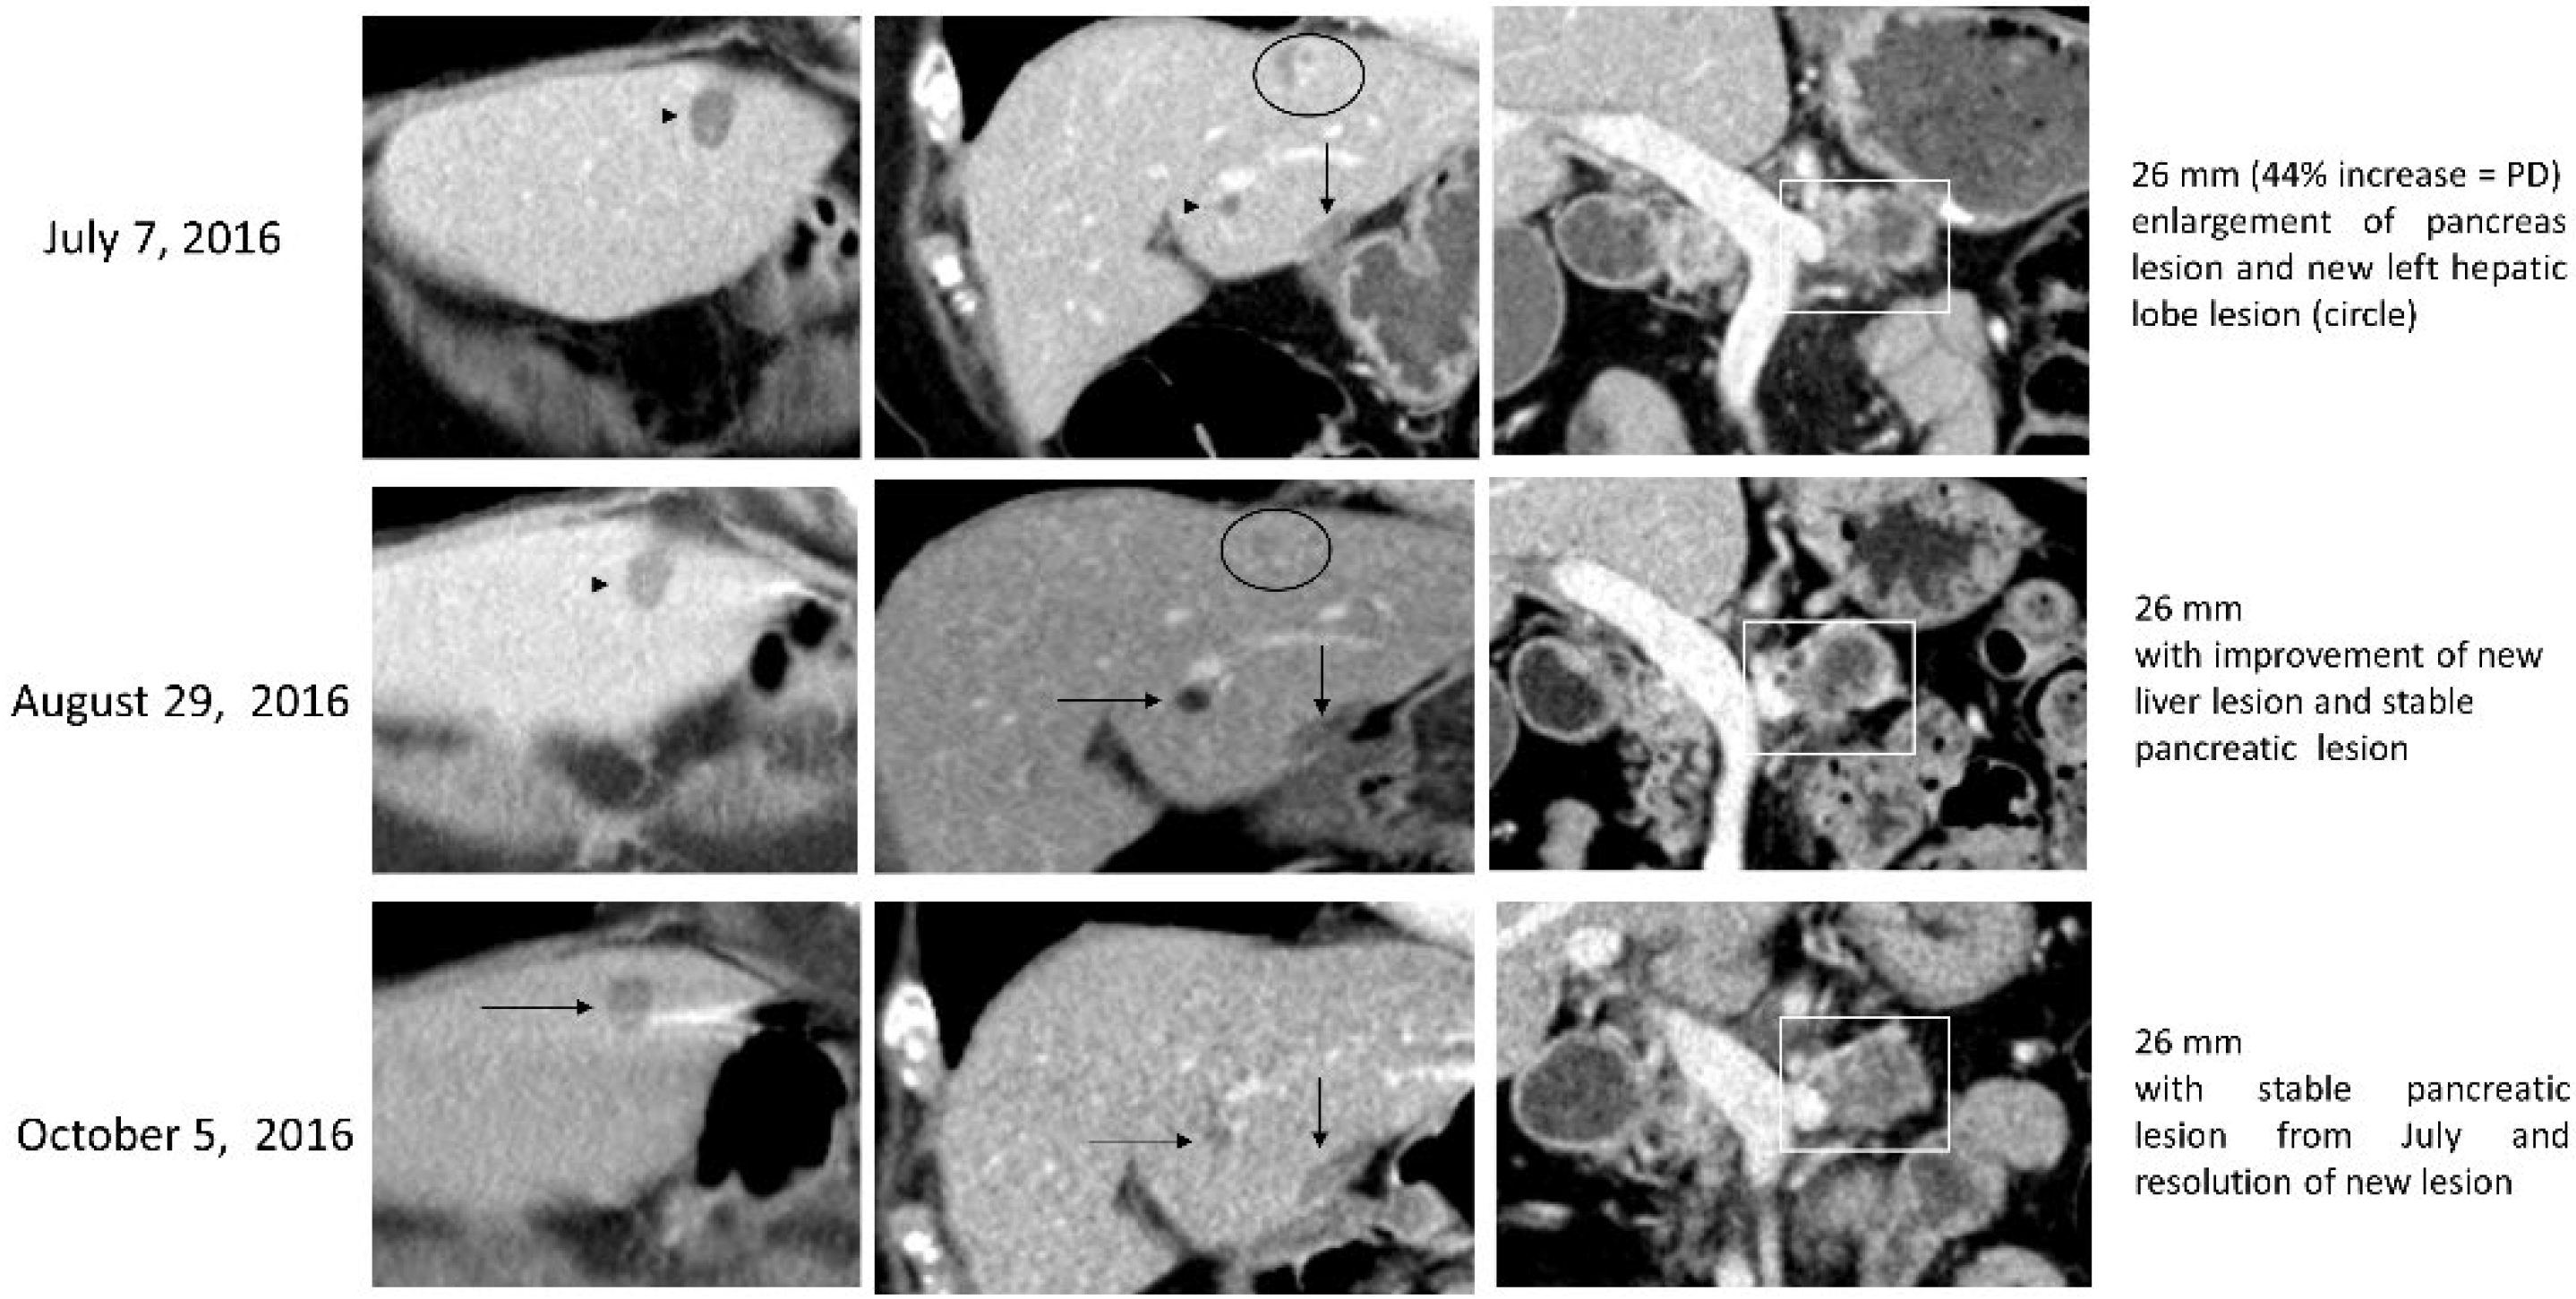

3.2.1. Case (1)